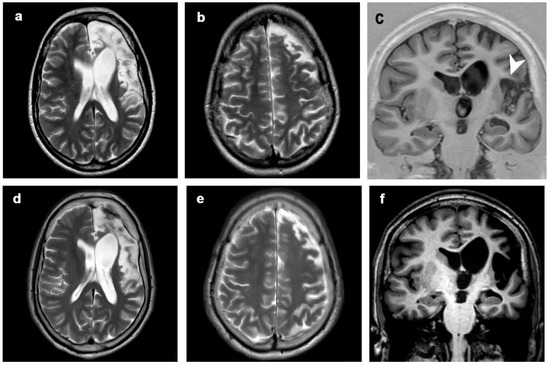

3.1. Atrophic Changes

3.2. Changes in Signal Intensity